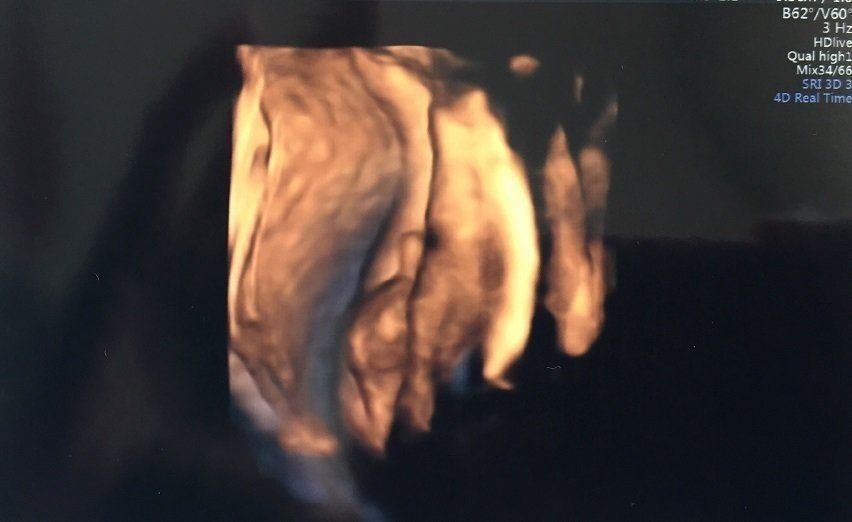

妊娠34週目のエコー写真 妊婦生活いよいよラストスパート!

どうやらおなかの赤ちゃんには、すでに髪の毛がしっかり生えているようで、眉毛もうっすら写っています。頭の髪の毛は黒々して、もう伸びているようにも見えます。頬の肉付きもだいぶ良くなり、顔全体がふっくらしています。この時点で推定体重は2500gを超えており、「少し大きい子だね」と言われていました。長女が2600g代で産まれてきているので、すでに近いサイズの赤ちゃんがおなかにいるのかと思うと、いよいよだと少し緊張しました。

エコー中も手を顔の近くでよく動かしており、顔の一部が手で隠れて黒くなっています。口も少し開いているようです。

足回りの骨もしっかり太くなり、だいぶがっちりしてきた印象です。私は以前貧血で鉄剤を処方されていましたが、今回の血液検査では正常。これで安心して出産に臨めると思いました。出産まで、あと残り1カ月ちょっとになり、次第に「長女の一人っ子生活も間もなく終わってしまう」と寂しさを感じるようになって、娘との時間を大切にしたいと感じていました。妊娠後期に入り無理はできませんでしたが、近場でたくさんお出かけをして娘との時間を惜しむように過ごしていました。